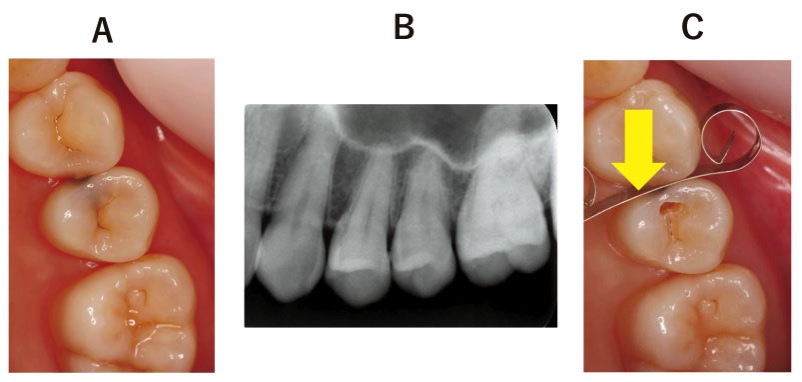

36歳の女性。上顎左側臼歯の冷水痛を主訴として来院した。上顎左側5にコンポジットレジン修復を行うこととした。初診時の口腔内写真、エックス線写真及びう蝕除去中の口腔内写真を別に示す。

矢印で示す器具の使用目的はどれか。1つ選べ。修復の隔壁

a 隔壁

b 防湿

c 歯問離開

d 歯肉排除

e 隣接歯保護

正答 e

この問題で、Cの写真に使われているのが、歯を削る時にでてくる隔壁です。問題を解く上では関係ないですが、この銀色のフィルムで歯を削る時に隣の歯を削ってしまわないようにガードしています。このガードのことを「隔壁」とも呼びます。問題では「目的」を聞かれているので、隣接歯保護が正答ですが、名前を聞かれたら、隔壁が答えにもなります。